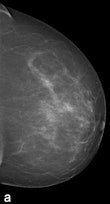

| Example of a subtle finding in a right-sided mediolateral oblique view, which was only reported by radiologists when using premium view (PV). A: Digitized prior. B: Tissue equalization (TE) processed image. C: PV processed image with the annotation. D: The resulting image of subtracting TE from PV. E: Thresholded version of D. White areas indicate that pixels in the PV image have relatively higher intensity than the related pixels in the TE image, whereas black areas indicate the opposite. In PV images, low-frequency trends are suppressed (no noticeable signal decrease in the breast edge in PV compared with TE), whereas higher-frequency structures are emphasized (e.g., glandular structures). All images courtesy of Wouter Veldkamp, PhD, Leiden University Medical Center. |

The cases were acquired using the Senographe Essential digital mammography system (GE Healthcare). Tissue equalization is a standard GE application that corrects for low-frequency variations resulting from under- and overpenetration of x-rays. As a result, the image dynamic range is reduced, enabling improved soft-copy image display.

The local contrast optimization, premium view, has been designed to improve the quality of the information presented to the radiologist for diagnosis and also the reading speed by optimizing the local contrast in breast structures. In premium view, low-frequency structures are obtained from the original image by low-pass filtering. High-frequency structures are obtained by subtracting the low-pass filtered image from the original image. The low- and high-frequency images are both processed and weighted individually, then added together. The resulting image exhibits reduced contrast between different tissue types but enhanced contrast of small-scale anatomical architecture.

Another example of a finding in a left-sided craniocaudal view that was reported clearly more often by radiologists when using premium view (PV). A: Tissue equalization (TE) processed image. B: PV processed image with the annotation. C: Similar to image above, the resulting image of subtracting TE from PV. D: The thresholded version of C.For all six radiologists, perceived case suspiciousness -- defined as the highest probability of malignancy of all radiologist findings -- was higher using premium view optimization.